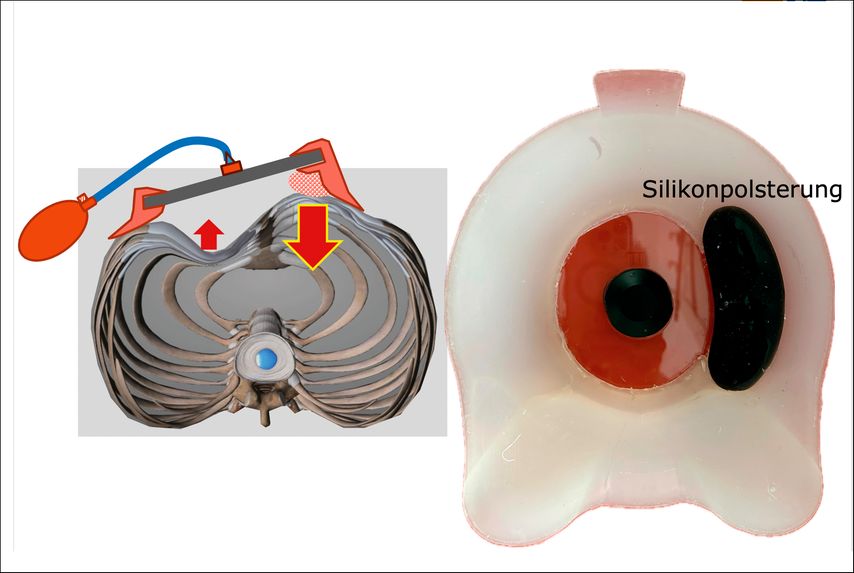

Für die spezielle Situation, in der vorgewölbte untere Rippenbögen („flared ribs“) vorhanden sind, bewährt sich als aktuelle innovative Entwicklung die Y-förmig gestaltete Unterdruck-Überdruck-Saugglocke® (Abb.4), die einerseits den Trichter abflacht, gleichzeitig aber auch eine Kompression auf vorspringende untere Rippenbögen (Abb.5) ausübt und die komplette Umformung provoziert. Alle Saugsysteme machen den Brustkorb grundsätzlich beweglicher.

Abb. 4: Unterdruck-Überdruck-Saugglockentherapie bei Trichterbrust mit vorspringenden Rippenbögen mit der Y-Saugglocke® (Fa. Götz Orthopädietechnik St. Pölten/Fa. Sanag Tulln)

Die Kompression auf vorspringende Areale der Thoraxwand, wie sie z.B. im Rahmen einer gemischten vertikalen Kiel-Trichterdeformität auftritt, kann durch zusätzliche, individuell angepasste Silikonkissen innerhalb der Saugglocke behandelt werden (Abb.6).

Abb. 6: Bei vertikaler Kiel-Trichterdeformität Unterdruck-Überdruck-Saugglockentherapie mit eingesetztem Silikonkissen als Pelotte in einer Y-Saugglocke® (Fa. Götz Orthopädietechnik St. Pölten/Fa. Sanag, Tulln)